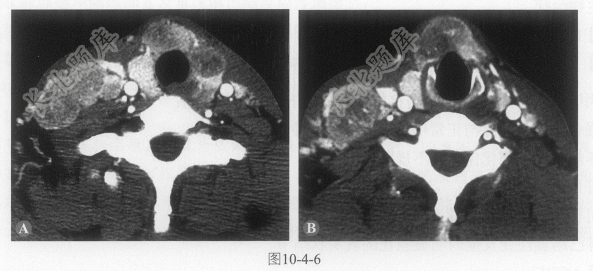

多项选择题2.该患者同时进行了颈部CT扫描(图10-4-6),关于CT影像表现,以下描述正确的是:

A、甲状腺左叶及峡部增大,内见低密度结节

B、病变边界较清楚,形态不规则,密度不均匀,强化较明显

C、双侧颈部Ⅳ区及Ⅵ区可见多发淋巴结,明显强化,右侧者较大

D、部分病变内可见钙化灶

E、结节内可见囊变及壁内乳头状结节